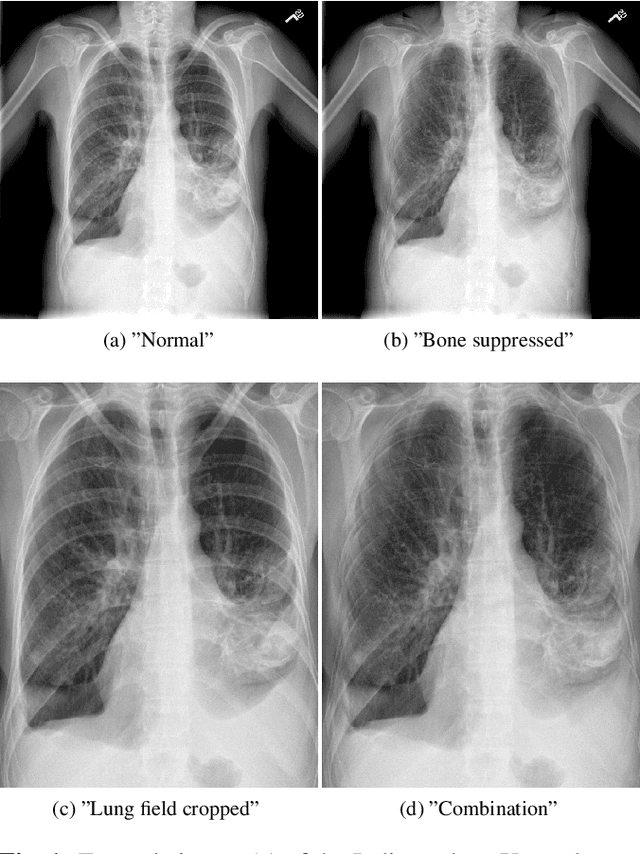

Abstract:Chest radiography is the most common clinical examination type. To improve the quality of patient care and to reduce workload, methods for automatic pathology classification have been developed. In this contribution we investigate the usefulness of two advanced image pre-processing techniques, initially developed for image reading by radiologists, for the performance of Deep Learning methods. First, we use bone suppression, an algorithm to artificially remove the rib cage. Secondly, we employ an automatic lung field detection to crop the image to the lung area. Furthermore, we consider the combination of both in the context of an ensemble approach. In a five-times re-sampling scheme, we use Receiver Operating Characteristic (ROC) statistics to evaluate the effect of the pre-processing approaches. Using a Convolutional Neural Network (CNN), optimized for X-ray analysis, we achieve a good performance with respect to all pathologies on average. Superior results are obtained for selected pathologies when using pre-processing, i.e. for mass the area under the ROC curve increased by 9.95%. The ensemble with pre-processed trained models yields the best overall results.